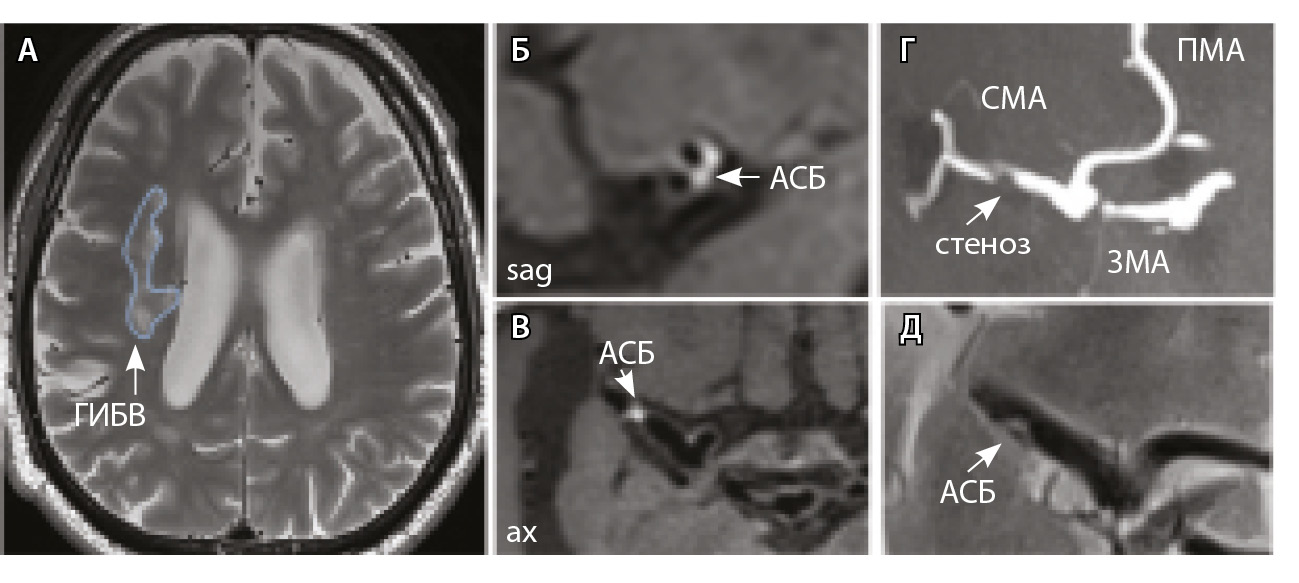

Рис. 3. Пациент Ц., 53 года, с признаками церебральной микроангиопатии (F3 по шкале Fazekas), атеросклерозом интракраниальных артерий, без формирования гемодинамически значимых стенозов. А – магнитно-резонансная томография (МРТ) головного мозга, режим Т2-взвешенного изображения: видны обширные сливные зоны гиперинтенсивности белого вещества (ГИБВ) с наличием на этом фоне лакунарных инфарктов; Б, В, Г – МРТ сосудистой стенки, режим T1-TSE-db-FS после контрастного усиления: в сегменте М1 левой средней мозговой артерии (СМА) визуализируется эксцентричная атеросклеротическая бляшка (АСБ), интенсивно накапливающая контрастный препарат; Д – трехмерная магнитно-резонансная времяпролетная (3D ToF) ангиография: выявляется неровность контуров левой СМА в сегменте М1; ax – аксиальная, sag – сагиттальная, cor – коронарная плоскости; ВСА – внутренняя сонная артерия; ПМА – передняя мозговая артерия